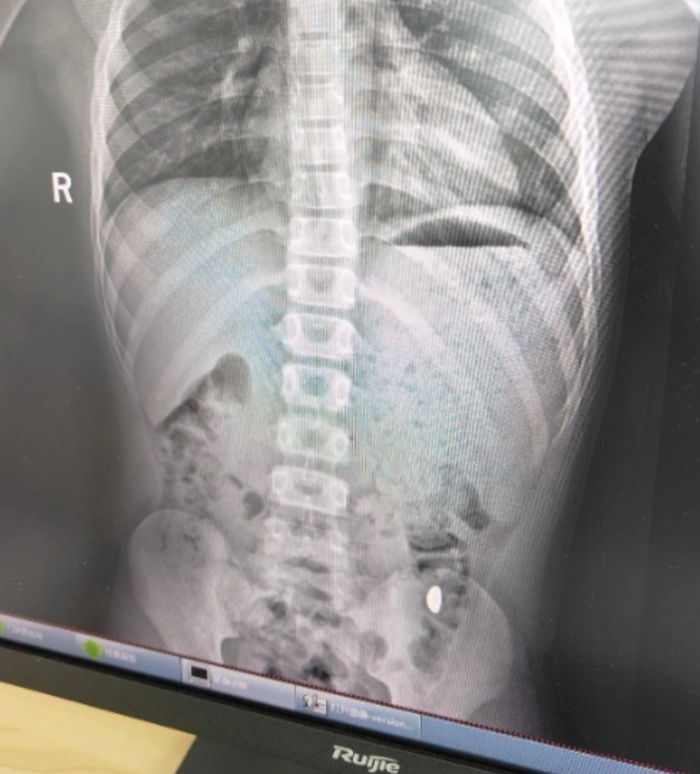

昆山市第五人民医院门诊病历单显示,患儿5天前误吞约10克黄金,其间解两次大便未发现,目前无腹痛、呕吐等症状,诊断结果显示胃内有异物。

图片

右下加亮点为金豆。